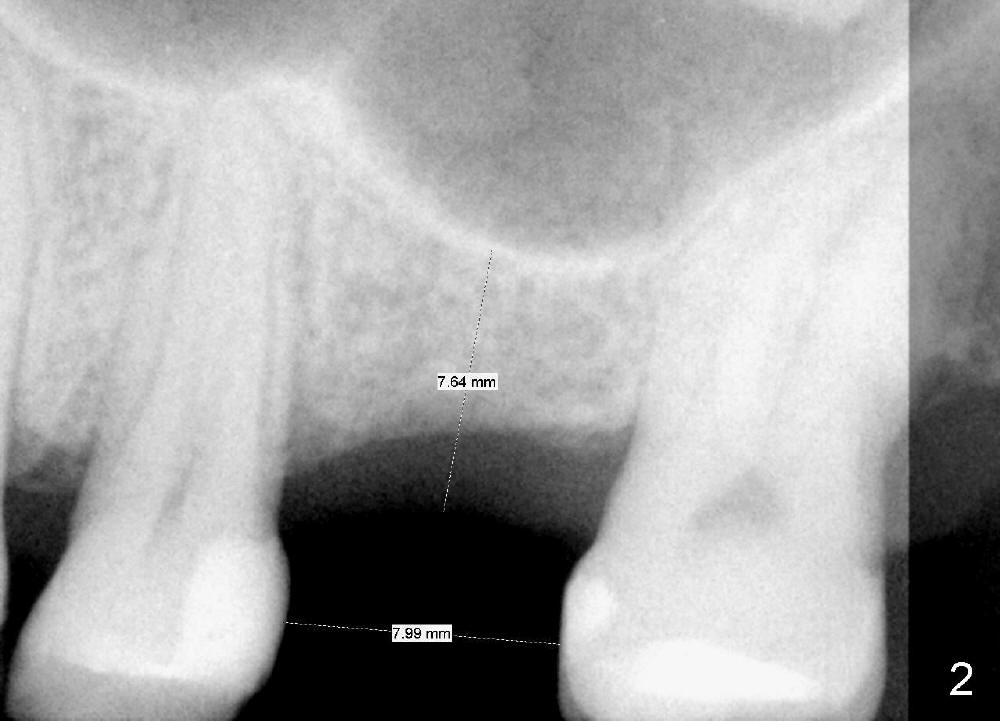

A 48-year-old lady has lost #14 for a while (Fig.1). It looks that bone density at the site of #14 is lower than that mesial to the 2nd premolar. The buccolingual width is wide clinically, although the mesiodistal distance is short (8 mm, Fig.2). A 4-mm tissue punch is used for access. When 1.5 mm pilot drill is used to start osteotomy, it feels that bone density is not low. The first bone expander (2.6 mm) cannot penetrate the bone. Therefore reamers 2.5-3.5 mm are used to increase osteotomy at the depth of 6 mm from the gingival margin. A 4.5x11 mm tap drill is inserted ~ 7 mm with resistance (Fig.3). After 5x11 mm tap, autogenous bone mixed with Osteogen is pushed into the osteotomy and upward. A 5x11 mm implant is placed with > 60 Ncm (Fig.4). After the last X-ray, the implant is torqued 5 more times so that the distal last thread may be able to be fully engaged to the bone. Fig.5 is CT coronal section at the site of #14 5 days postop (B: buccal; L: lingual). Fig.6 is taken 5 months postop with maintenance of sinus lift (*). The crown dislodges 16 months post cementation. In fact the abutment is also loose. The latter is resin bonded, followed by crown cementation (Fig.7). It appears that when the implant is 5 mm or less, the unipost should be permanently cemented in order to prevent crown displacement, particularly for a patient with bruxism and partial edentulism.